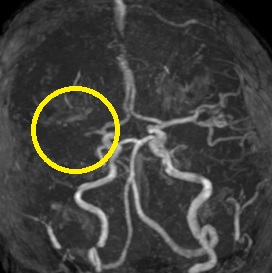

超急性期脳梗塞に対する血栓溶解療法(t-PA治療)

ろれつ困難と左半身重度麻痺のため当院に救急搬送となった患者様に対し、発症2時間30分でt-PAの投与を開始。t-PA開始1時間半後に左麻痺とろれつ困難は回復し始め、翌日には症状は消失。t-PA後のMRA検査で閉塞血管の完全再開通を認め、発症から2週間後に神経症状なく退院。

(来院時MRA検査画像)